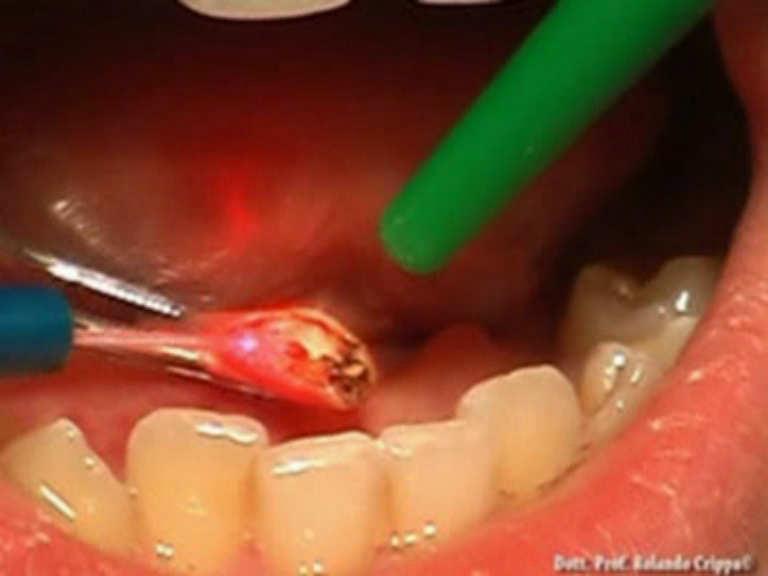

Laser setting

Diode Laser 810nm

Power 2.5 Watt,

pulsed 50 Hz

Time On/Off 10ms

Fibre 400 micron